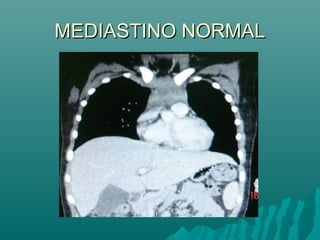

MEDIASTINO NORMALMEDIASTINO NORMAL

Ventana en TCARVentana en TCAR

 «El grosor de la pared bronquial en TCAR deberá«El grosor de la pared bronquial en TCAR deberá

estudiarse, con un nivel de ventana entre -250 yestudiarse, con un nivel de ventana entre -250 y

-700 UH y una amplitud de ventana mayor de-700 UH y una amplitud de ventana mayor de

1,000 UH.1,000 UH.

 Con una amplitud de ventana inferior a 1,000 UHCon una amplitud de ventana inferior a 1,000 UH

se producirá un engrosamiento artificial de lase producirá un engrosamiento artificial de la

pared bronquial.pared bronquial.

Ortega M y col. Utilidad de la radiografía de tórax yOrtega M y col. Utilidad de la radiografía de tórax y

de la tomografía computada de alta resolución»de la tomografía computada de alta resolución»

Alergia , asma e inmunologia pediatricaAlergia , asma e inmunologia pediatrica

Vol20,num3 sep-dic 2011Vol20,num3 sep-dic 2011